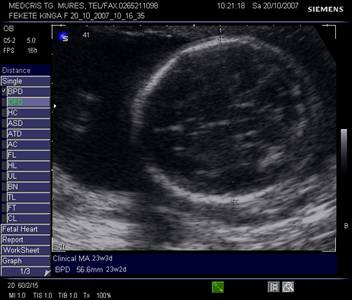

Capul - planul corect de referinta permite masurarea in aceeasi sectiune a celor trei parametri BPD, OFD, HC

Planul

cuprinde o sectiune occipitofrontala transversala simetrica, ovoidala, cu

prezenta distincta a ecoului de mijloc, cavum septum pellucidi in 1/3

anterioara si nucleii talamici .

Fig. nr.198. Masurarea diametrului biparietal ( BPD )

Fig. nr.199. Masurarea diametrului occipitofrontal (OFD ) si a circumferintei craniene ( HC)